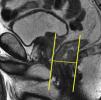

Tras el localizador inicial es recomendable realizar 3 secuencias rápidas de disparo único (single shot) ponderadas en T2 en los 3 planos para tener una mejor visión de la región a explorar y una mayor aproximación al área afectada. A continuación han de emplearse las secuencias de alta resolución FSE ponderadas en T2. En primer lugar ha de obtenerse una serie en plano sagital estricto de todo el mesorrecto que, además de aportar información para el diagnóstico (extensión cráneo-caudal del tumor y grado de infiltración), debe servir para planificar las demás secuencias con precisión. Seguidamente han de obtenerse planos perpendiculares y paralelos al eje longitudinal del recto que incluyan el mesorrecto en toda su extensión, desde el promontorio del sacro hasta el margen anal y desde el septo urogenital hasta el sacro (figs. 7 y 8). El objetivo de estas secuencias es evaluar posibles adenopatías mesorrectales y estudiar la posibilidad de aplicar implantes. Llegados a este punto, según el tercio del recto en estudio, es necesario obtener planos oblicuos directamente sobre la masa tumoral:

Han de obtenerse planos axiales oblicuos que cubran el tumor en toda su extensión y queden orientados perpendicularmente a su eje cráneo-caudal en el plano sagital (fig. 9). Las imágenes resultantes permiten evaluar el propio tumor y la afectación de la pared rectal y del mesorrecto, así como la afectación de las estructuras y órganos pélvicos.